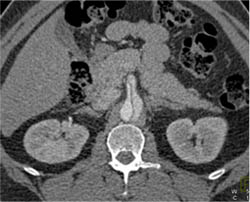

CTA of Pancreas